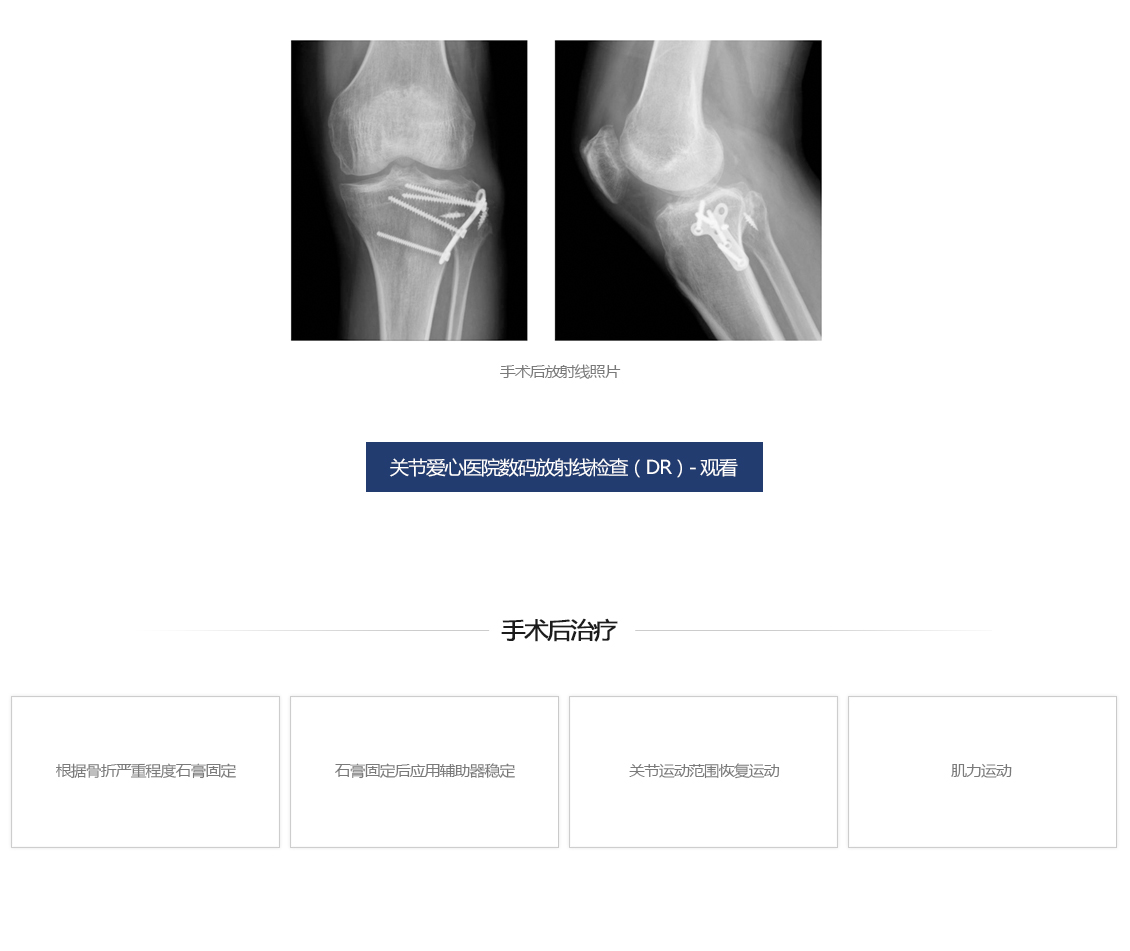

膝盖骨折手术